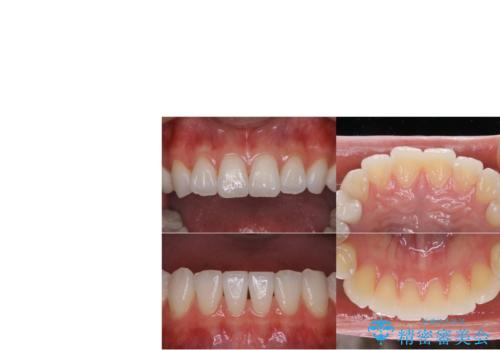

元々噛む力が強く、日常的に歯ぎしりもされるとの事で、セラミックが欠けてしまっていました。歯が割れてしまうリスクを軽減させるため、歯全体を覆うクラウンをメインに補綴治療を行いました。

右上の小臼歯部においては、元々はセラミックインレーでの治療をご提案していましたが、歯や被せ物がまた割れてしまうのが嫌との事で、患者様よりクラウンにしてほしいとの強いご希望がありました。元々の欠損部の面積に対して歯を全周削ることになるため、オーバートリートメントになってしまう事を十分ご説明し、ご納得頂いた上でクラウンによる補綴処置を行いました。

被せ物の色は患者様のご希望により明るめの色(A1)にて作製しております。